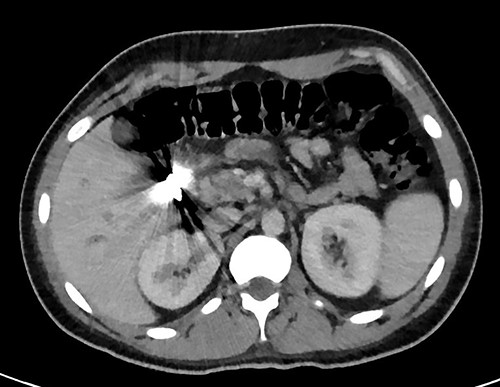

A full lab panel was ordered and revealed a total bilirubin of 1.1, direct bilirubin 0.5, lactate dehydrogenase 196, alkaline phosphatase 80, aspartate transaminase 46 and alanine transaminase 58. A computed tomography (CT) angiographic scan of the chest, abdomen and pelvis revealed the presence of a rim enhancing fluid collection in hepatic segment V with internal gas and containing a metallic foreign body, measuring 8 × 5 cm and consistent with abscess formation (Figs 2–4). The linear tract of the bullet in the right iliac crest was visualized in the CT as well.

Transverse plan of the CT showed the bullet lodged in segment 5 of the liver.